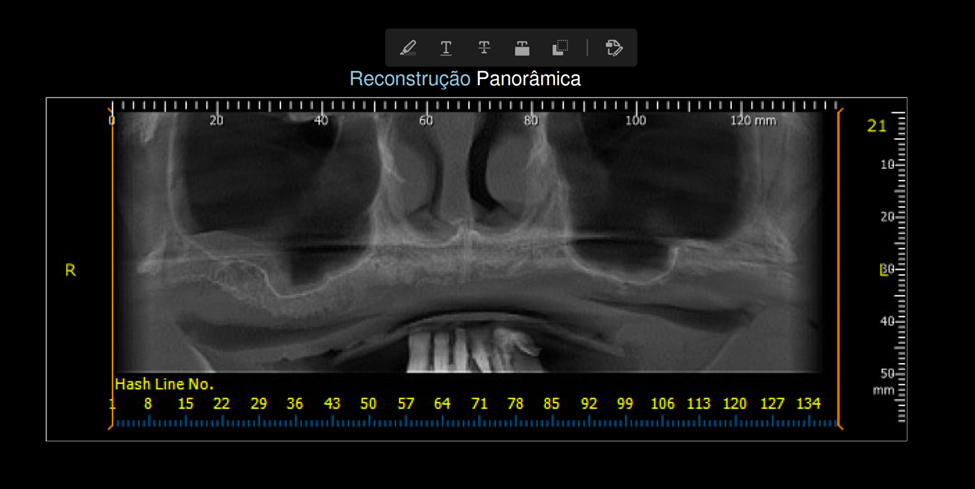

No presente caso, uma paciente de 78 anos nos procurou para realizar implantes e uma prótese total fixa (do tipo protocolo Brånemark). Ao solicitar a tomografia, constatamos a necessidade de realizar uma cirurgia reconstrutiva (de enxertia óssea) prévia à cirurgia de implantes, pois não havia a mínima quantidade óssea necessária (Foto 1). Optamos por uma cirurgia de Levantamento de Seio Maxilar bilateral devido às maiores chances de ganho ósseo em comparação a uma reconstrução na região anterior (que estava demasiadamente reabsorvida). A paciente foi encaminhada para um cirurgião bucomaxilofacial, para realizar a cirurgia em ambiente hospitalar, considerando-se a idade avançada e o grau de morbidade do procedimento cirúrgico.

Aguardado o tempo de Osseointegração do enxerto (em torno de oito meses), solicitamos uma nova tomografia, onde foi observado ganho ósseo suficiente para a instalação de implantes, apesar de ainda ser uma condição limítrofe (Fotos 2, 3 e 4). O planejamento cirúrgico foi de instalar cinco implantes, sendo dois no lado direito e três no lado esquerdo, onde a extensão de ganho ósseo foi maior e possibilitava distribuir melhor os implantes.